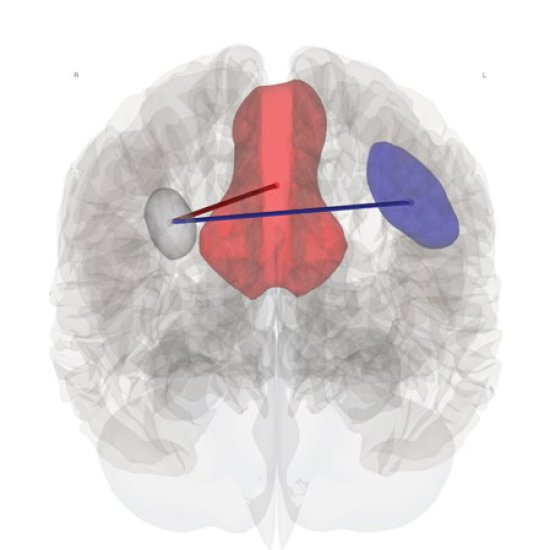

News • Altered brain connection

Brain fog explained: People with ME/CFS and long Covid experience a disruption to their brain connectivity during a mentally demanding task, new research finds. |